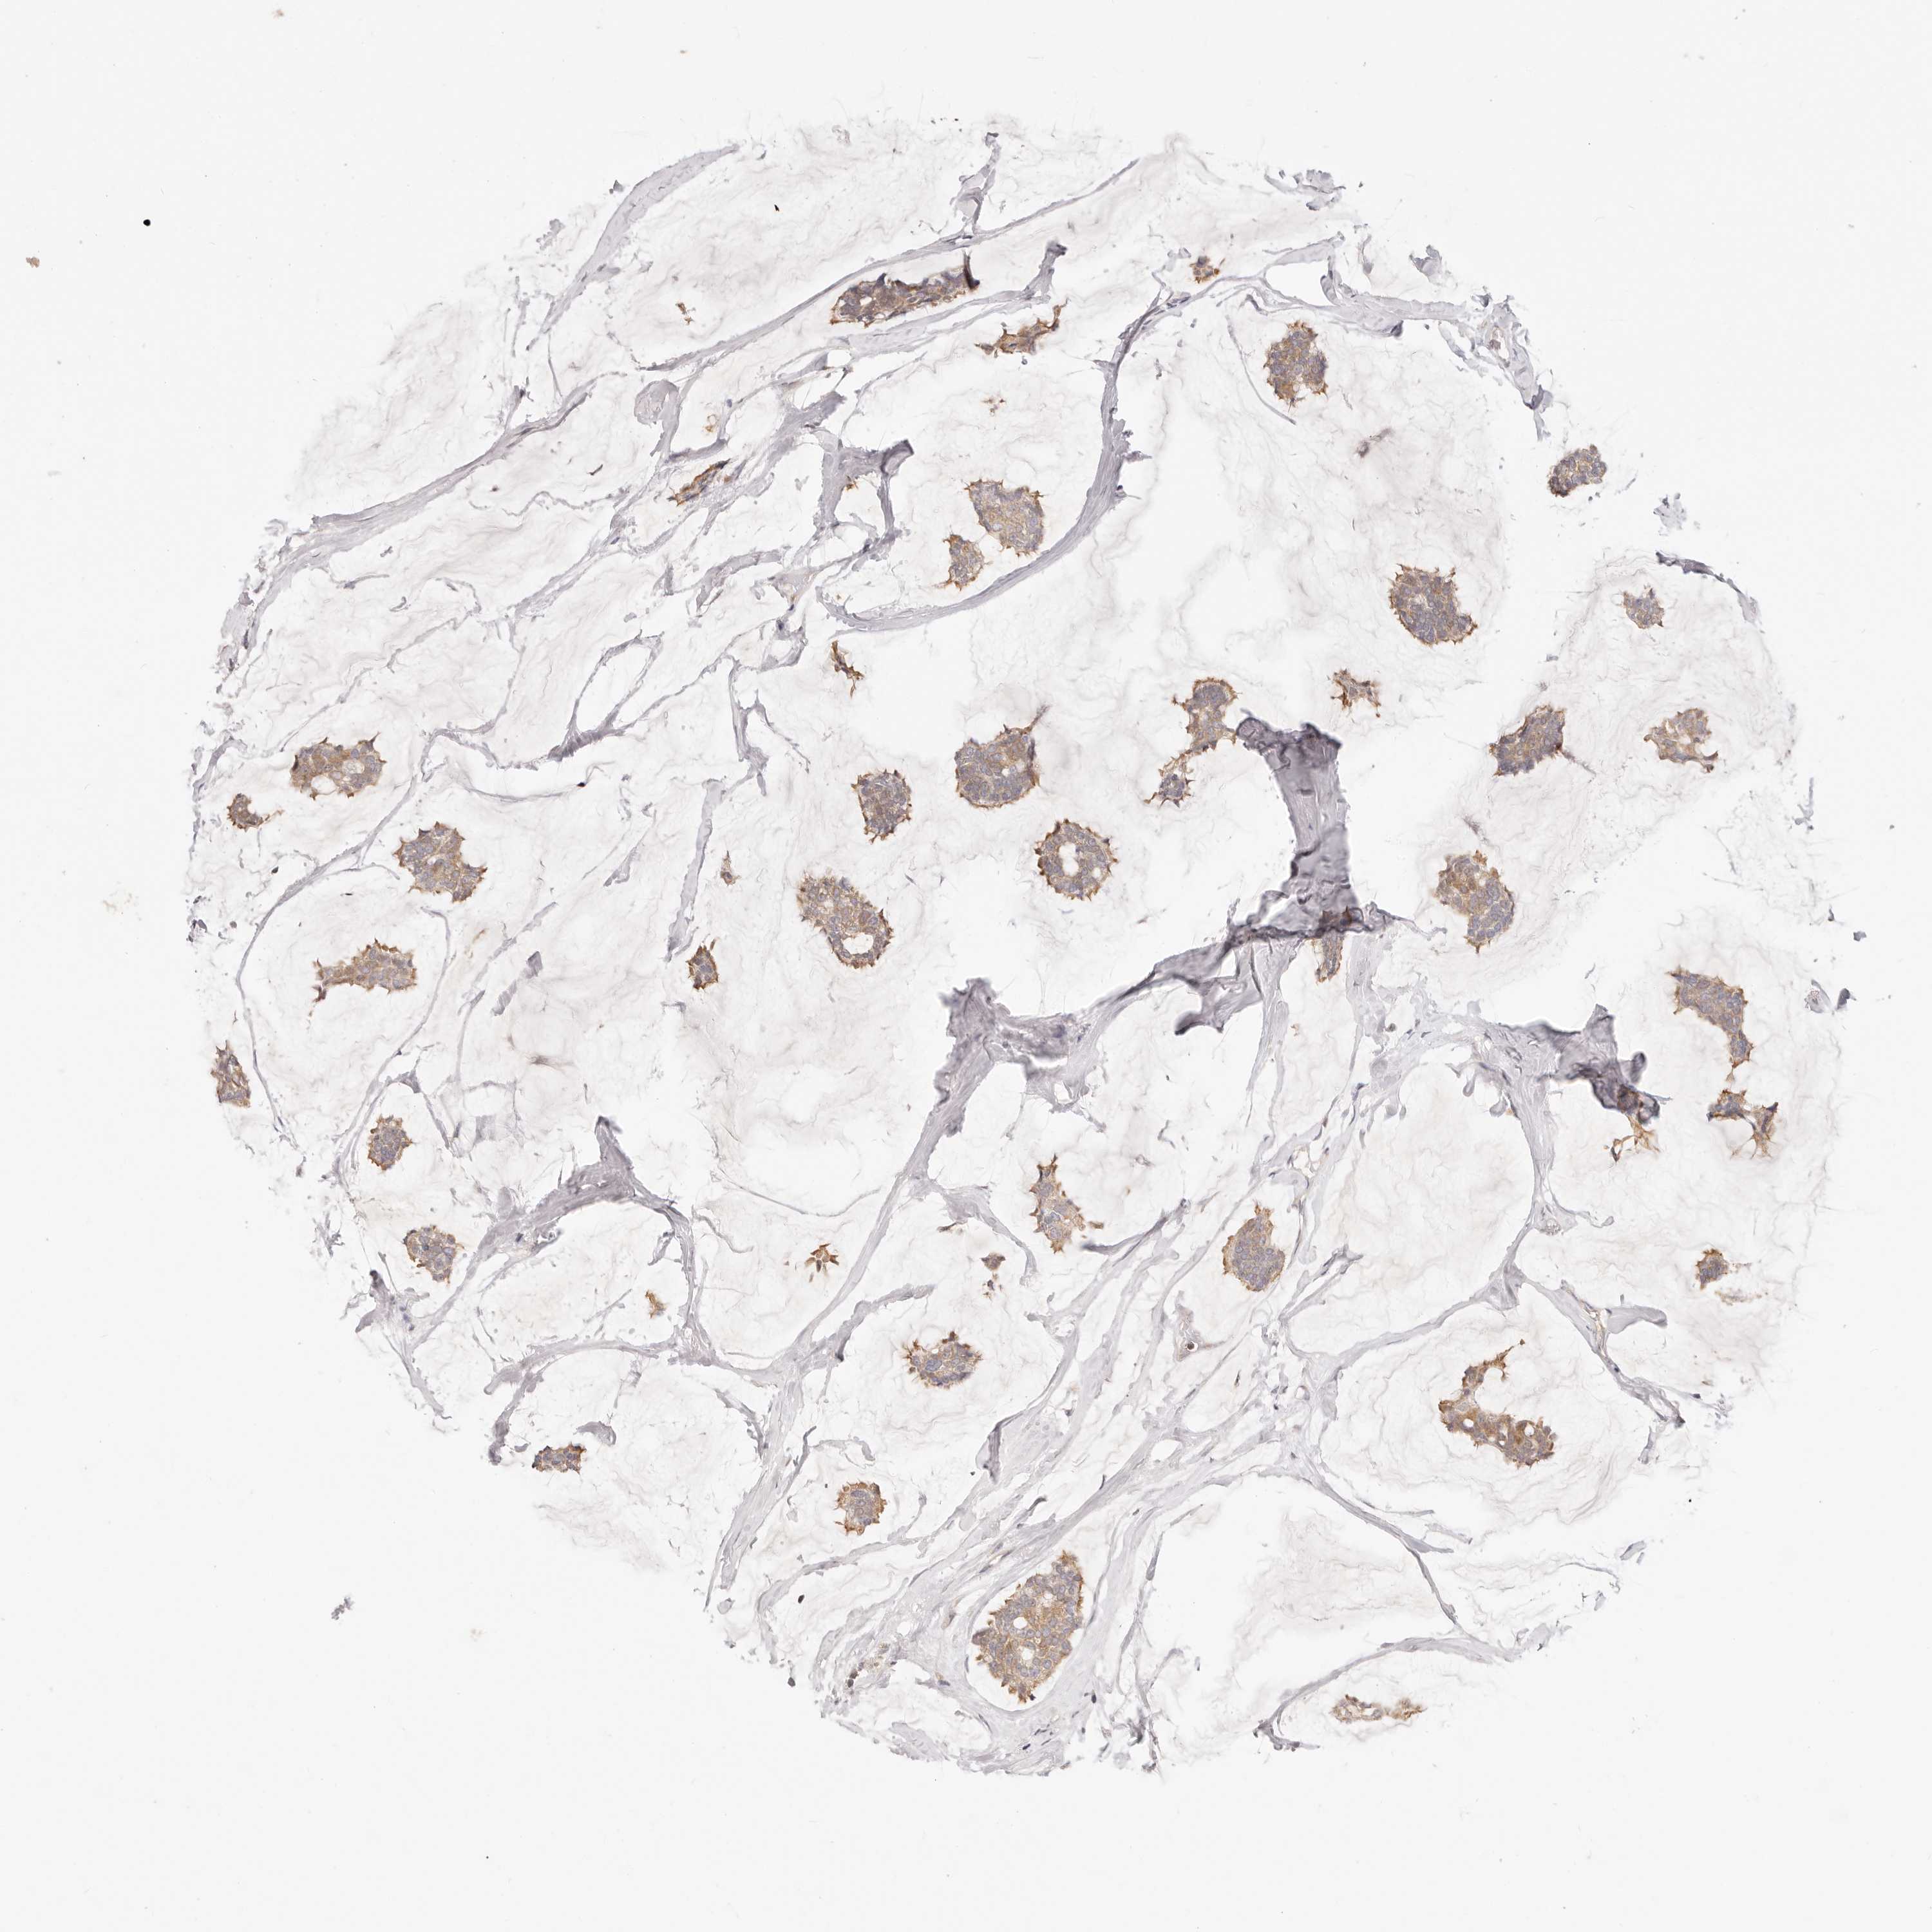

CANCER BREAST CANCER Show tissue menu

BRCA TCGA BRCA VALIDATION PROTEIN EXPRESSION